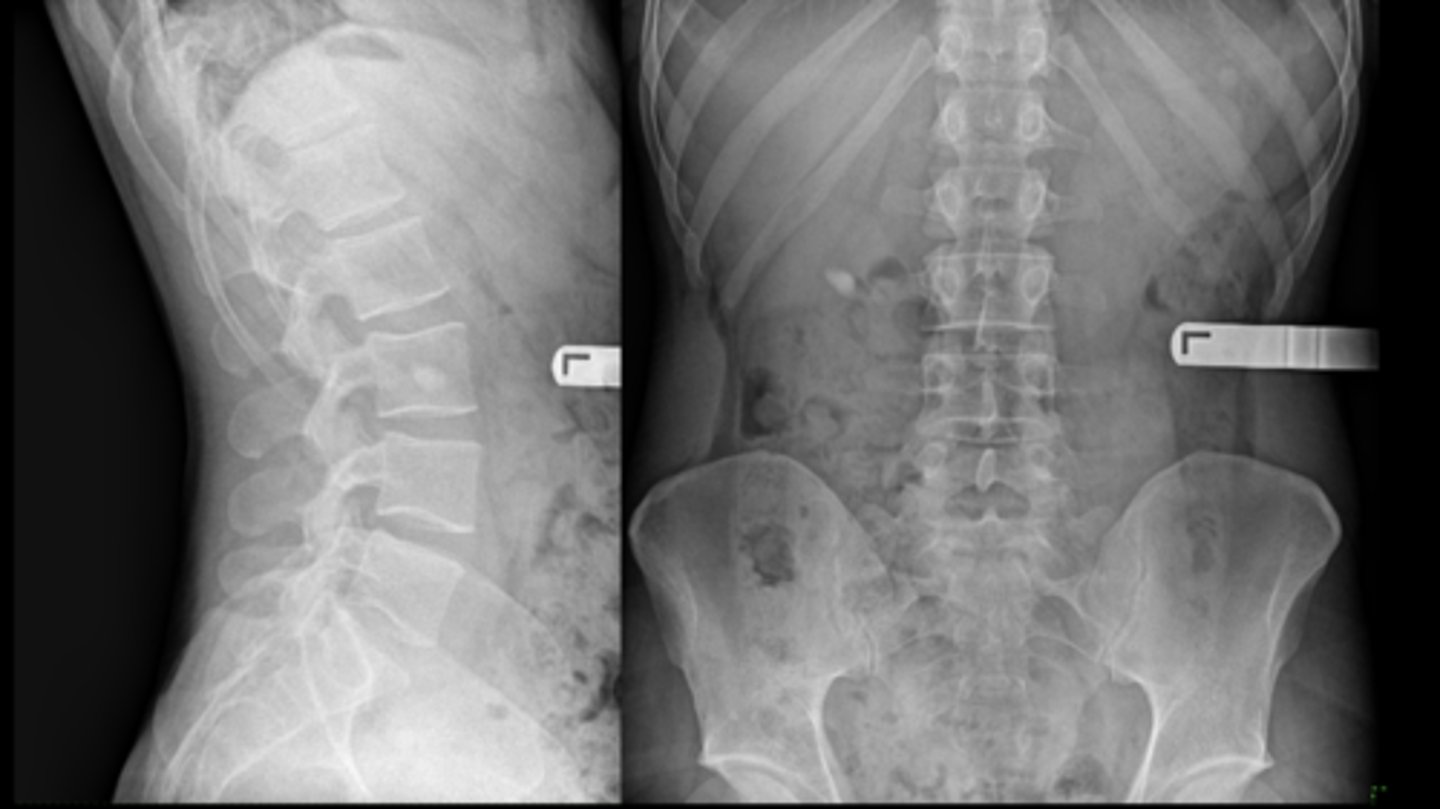

Giant bone islands

ID

- Bone island

- Kidney stone*

22 y.o. male with L/S pain, post motor vehicle accident

- Differential diagnosis?

Osteopoikilosis

Diagnosis?